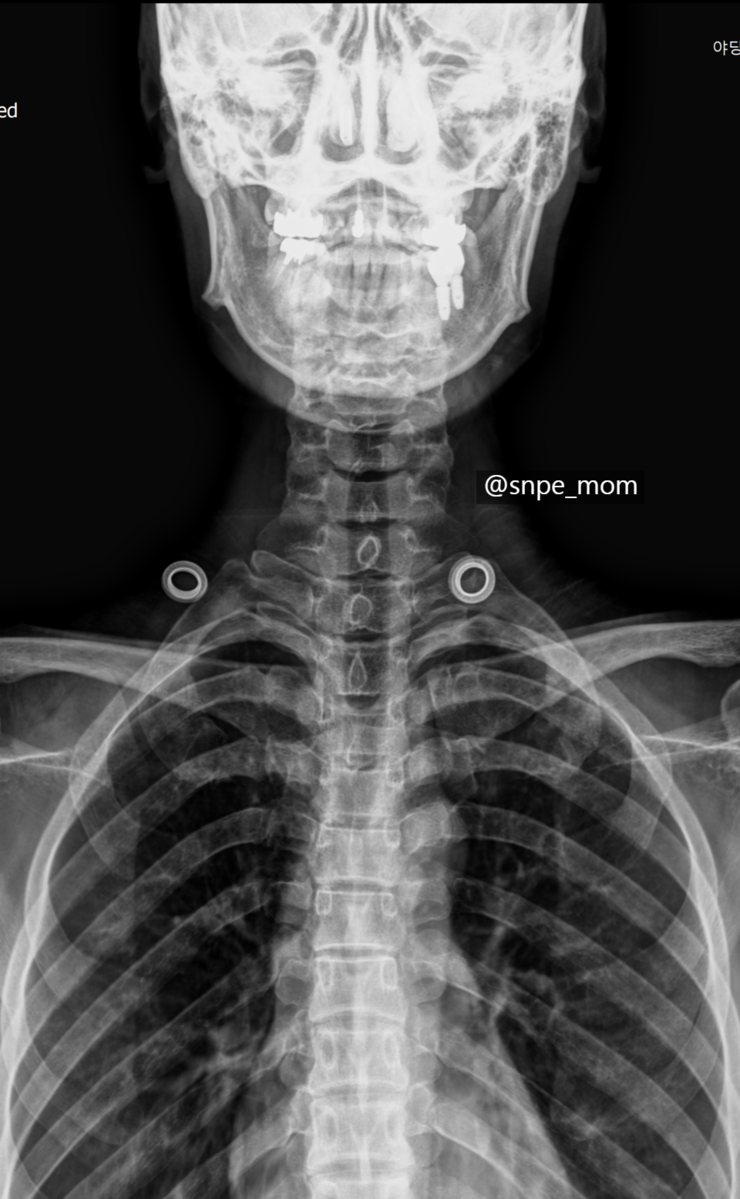

척추를 바로잡아야 건강이 보인다 51페이지에 바르지 못한 자세는 치아 건강에 영향을 준다는 ~ 내용이 너무 공감을 했습니다. 아래 사진은 제 엑스레이 사진인데요. 치아 부분에 햐얗게 된 부분이 ~ 다 치료한 이에요~;;  경추 1번이 보이기 위해서 입을 벌리고 찍으면 참 좋았을텐데, 아쉽지만 ~ 그래도 씌운 이의 압박이 보이시나요?ㅠ